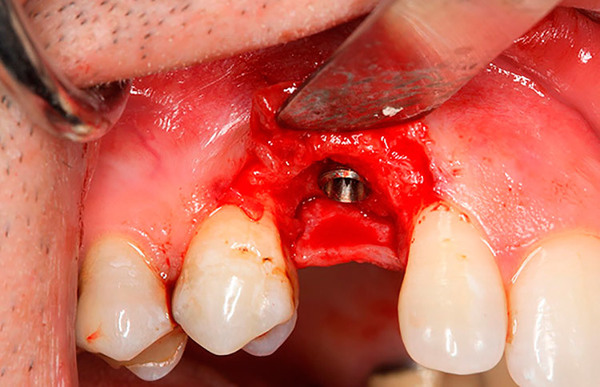

- Вкручивание стрежня — на место удалённого зуба устанавливается стержень. Для наилучшей фиксации врач может сделать прокол. Продолжительность процедуры составляет 30 минут.

- Малая травматичность процедуры ввиду небольшого прокола.